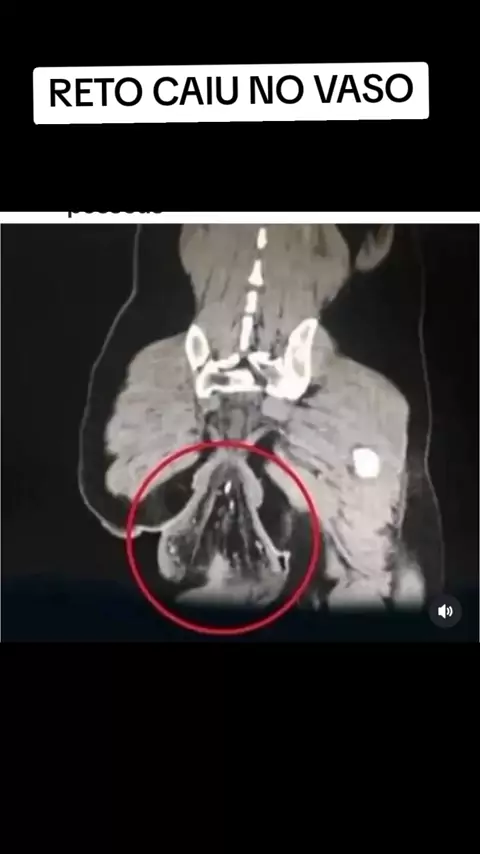

RETO CAIU NO VASO